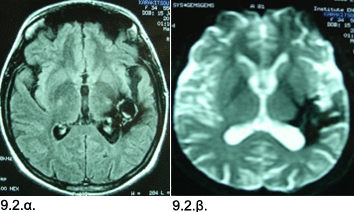

Εικόνες 9.2.α. & 9.2.β. Μαγνητική τομογραφία πού δείχνει την πλήρη αφαίρεση του αιματώματος και του σηραγγώδους αιμαγγειώματος, δια μέσου μίας ελάχιστα επεμβατικής χειρουργικής προσπέλασης σε εγκάρσια τομή Τ1 [9.2.α.], και άλλη απεικόνιση Τ2 [9.2.β].

Ιστορικό: Γυναίκα 35 ετών, με αιφνίδια και ταχέως επιδεινούμενη κεφαλαλγία, μεγάλη αδυναμία χεριού και ποδιού δεξιά, και μεγάλη δυσχέρεια εκφοράς του λόγου (κινητική αφασία). Κατά τον απεικονιστικό έλεγχο διαπιστώθηκε ένα μεγάλο αιμάτωμα, διαμέτρου 4.5 εκ. στην συμβολή κροταφικού, βρεγματικού και ινιακού λοβού αριστερά. Στην εξέταση, διαπιστώθηκε δεξιά κροταφική ημιανοψία. Η ασθενής υποβλήθηκε σε επείγουσα κρανιοτομία αριστερά και αφαίρεση του αιματώματος και του σηραγγώδους αιμαγγειώματος που είχε ραγεί. Η μετεγχειρητική πορεία ήταν ομαλή και η ασθενής δεν ανέπτυξε άλλα νευρολογικά προβλήματα. Μέσα στο πρώτους έξι μήνες, βελτιώθηκε πλήρως η μυϊκή αδυναμία και αποκαταστάθηκε σχεδόν πλήρως η ομιλία.